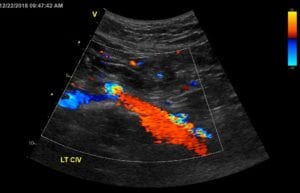

Authors: Tae An Choi ANP-BC, & Back Kim MD FACC. Heart Vein NYC, New York, New York Before (Right): 50 year-old male, a retail sales read more